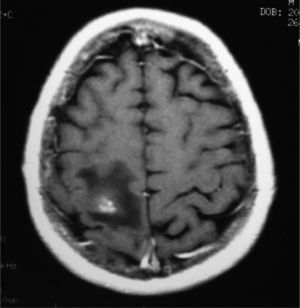

Los tumores primarios cardíacos son una entidad poco común. Su incidencia varía entre el 0,0017 y el 0,033% según las series consultadas1,2. En autopsias sistemáticas se encuentran en el 0,2% de los casos y la mayoría son benignos (90%)1. Entre los tumores cardíacos primitivos malignos destacan, por su frecuencia, los sarcomas (76-78%), y el angiosarcoma es el más frecuente en adultos1–3, que predomina entre la segunda y la quinta década de la vida3 y en el sexo masculino2–4. Dos tercios de los angiosarcomas se localizan en la aurícula derecha aun cuando tienen mejor pronóstico los alojados en la aurícula izquierda. Caso clínico: varón caucásico de 45 años de edad, sin alergias conocidas ni antecedentes personales de interés. Ex fumador de 10 cigarrillos desde hace 2 años. Sin hábitos tóxicos. En su historia familiar destaca el fallecimiento de su padre a los 57 años por neoplasia gástrica, el de su madre a los 65 años por melanoma con enfermedad ósea diseminada, el de su hermano a los 45 años por neoplasia de pulmón, su hermana a los 42 años por metástasis cerebral con neoplasia de pulmón primaria y otra hermana a los 57 años por sarcoma hepático. Encontrándose previamente bien presentó crisis focal (clonía del hemicuerpo izquierdo) con posterior generalización. En la exploración neurológica se objetivó disartria y paresia crural distal izquierda (4/5) con Babinski. La auscultación cardíaca fue rigurosamente normal. En las pruebas complementarias realizadas no se observaron alteraciones significativas en hemograma, bioquímica, inmunidad, coagulación ni gasometría arterial. Las serologías realizadas para descartar lesiones cerebrales de origen infeccioso (VIH, citomegalovirus, toxoplasma) fueron negativas. Se objetivó elevación de la enolasa sérica (33,6ng/ ml) con normalidad de los demás marcadores tumorales. Las pruebas de neuroimagen realizadas (tomografía computarizada [TC] y resonancia magnética [RM] cerebral) (fig. 1) revelaron una imagen compatible con metástasis única parietal derecha con pequeña hemorragia concomitante. Una TC torácica (fig. 2) reveló nódulos pulmonares metastásicos y una tumoración en la aurícula derecha informada en el ecocardiograma como imagen neoformativa de 59 × 42 × 30mm, redondeada, amplia base de implantación, densidad variable, bordes policíclicos con pequeñas zonas móviles en su superficie. El resto del estudio (broncoscopia, gammagrafía ósea, colonoscopia, pruebas funcionales respiratorias) fue normal. La biopsia de un nódulo pulmonar mediante toracoscopia fue compatible con angiosarcoma cardíaco en estadio IV. El paciente fue tratado con radioterapia holocraneal y quimioterapia paliativa con taxol semanal a dosis de 127,5mg, descartándose la cirugía, y falleció a los pocos meses por complicaciones infecciosas secundarias. El angiosarcoma cardíaco, por su baja frecuencia y su dificultad diagnóstico-terapéutica, supone un reto clínico importante. Dadas su agresividad y la frecuencia de metástasis al diagnóstico, las opciones de tratamiento son limitadas2. La mayoría de las veces es asintomático hasta fases avanzadas del proceso5. La clínica de presentación es muy variada, bien por crecimiento local del tumor (alteración del flujo cardíaco o de la función valvular) que va afectando al pericardio y estructuras vecinas (pericarditis, taponamiento cardíaco, arritmias, embolia tumoral) o bien por su extensión a distancia2–5. Las metástasis son frecuentes al diagnóstico de la enfermedad y los pulmones, hígado y cerebro son las localizaciones más habituales2, hecho que empeora de forma clara el pronóstico1,4,5. La supervivencia de los pacientes oscila en 9–12 meses tras el diagnóstico si no se puede resecar el tumor1,3. En general, el desarrollo de las pruebas de imagen (TC helicoidal y RM) ha mejorado el diagnóstico antes de la cirugía1,5. El tratamiento indicado de forma generalizada en pacientes sin enfermedad a distancia es la cirugía resectiva radical en combinación con quimioterapia y/o radioterapia adyuvante1,2. Algunos autores proponen el trasplante cardíaco como alternativa quirúrgica; sin embargo, las supervivencias obtenidas no difieren de las conseguidas con cirugía convencional1,2,5.